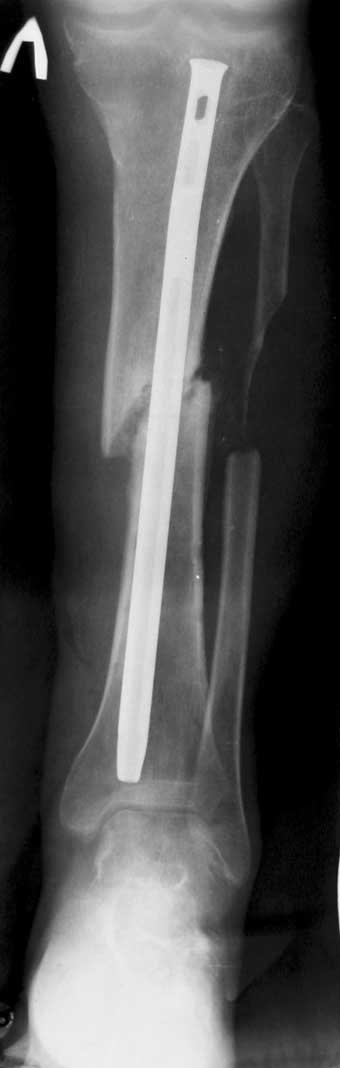

С места аварии в районную больницу, где произвели ампутацию правой голени. Дальше в клинику спец. помощи, где на левой голени были удалены нежизнеспосбные инфицированные отломки, (дефект 13 см) и наложен аппарат Гофмана. Детали неизвестны. Со слов больного, инфекционный процесс левой голени купирован не был. В феврале аппарат был снят и произведен остеосинтез гвоздем (before1;2). В мае, объективно: В нижней трети голени функционирует свищ, отделяемое гнойное: золотистый стафилокок, чувствительный к большинству антибиотиков.

1 июня произведено удаление гвоздя, дренаж костномозгового канала, остеосинтез аппаратом Илизарова ( after 1; 2).